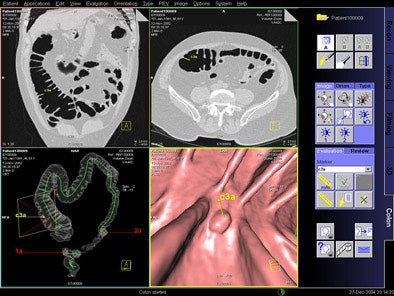

| Above, Siemens investigational VC CAD system. A marker ("c3a") is visible in the endoluminal view (lower right) representing a lesion proposed by the CAD system for physician review. The "c" indicates that it was automatically located. The other two markers (1a and 2a), also visible in the global view at lower left, were placed by the physician during the first read. The marker is highlighted in yellow because it is the one being reviewed. Images courtesy of Dr. Luca Bogoni. |